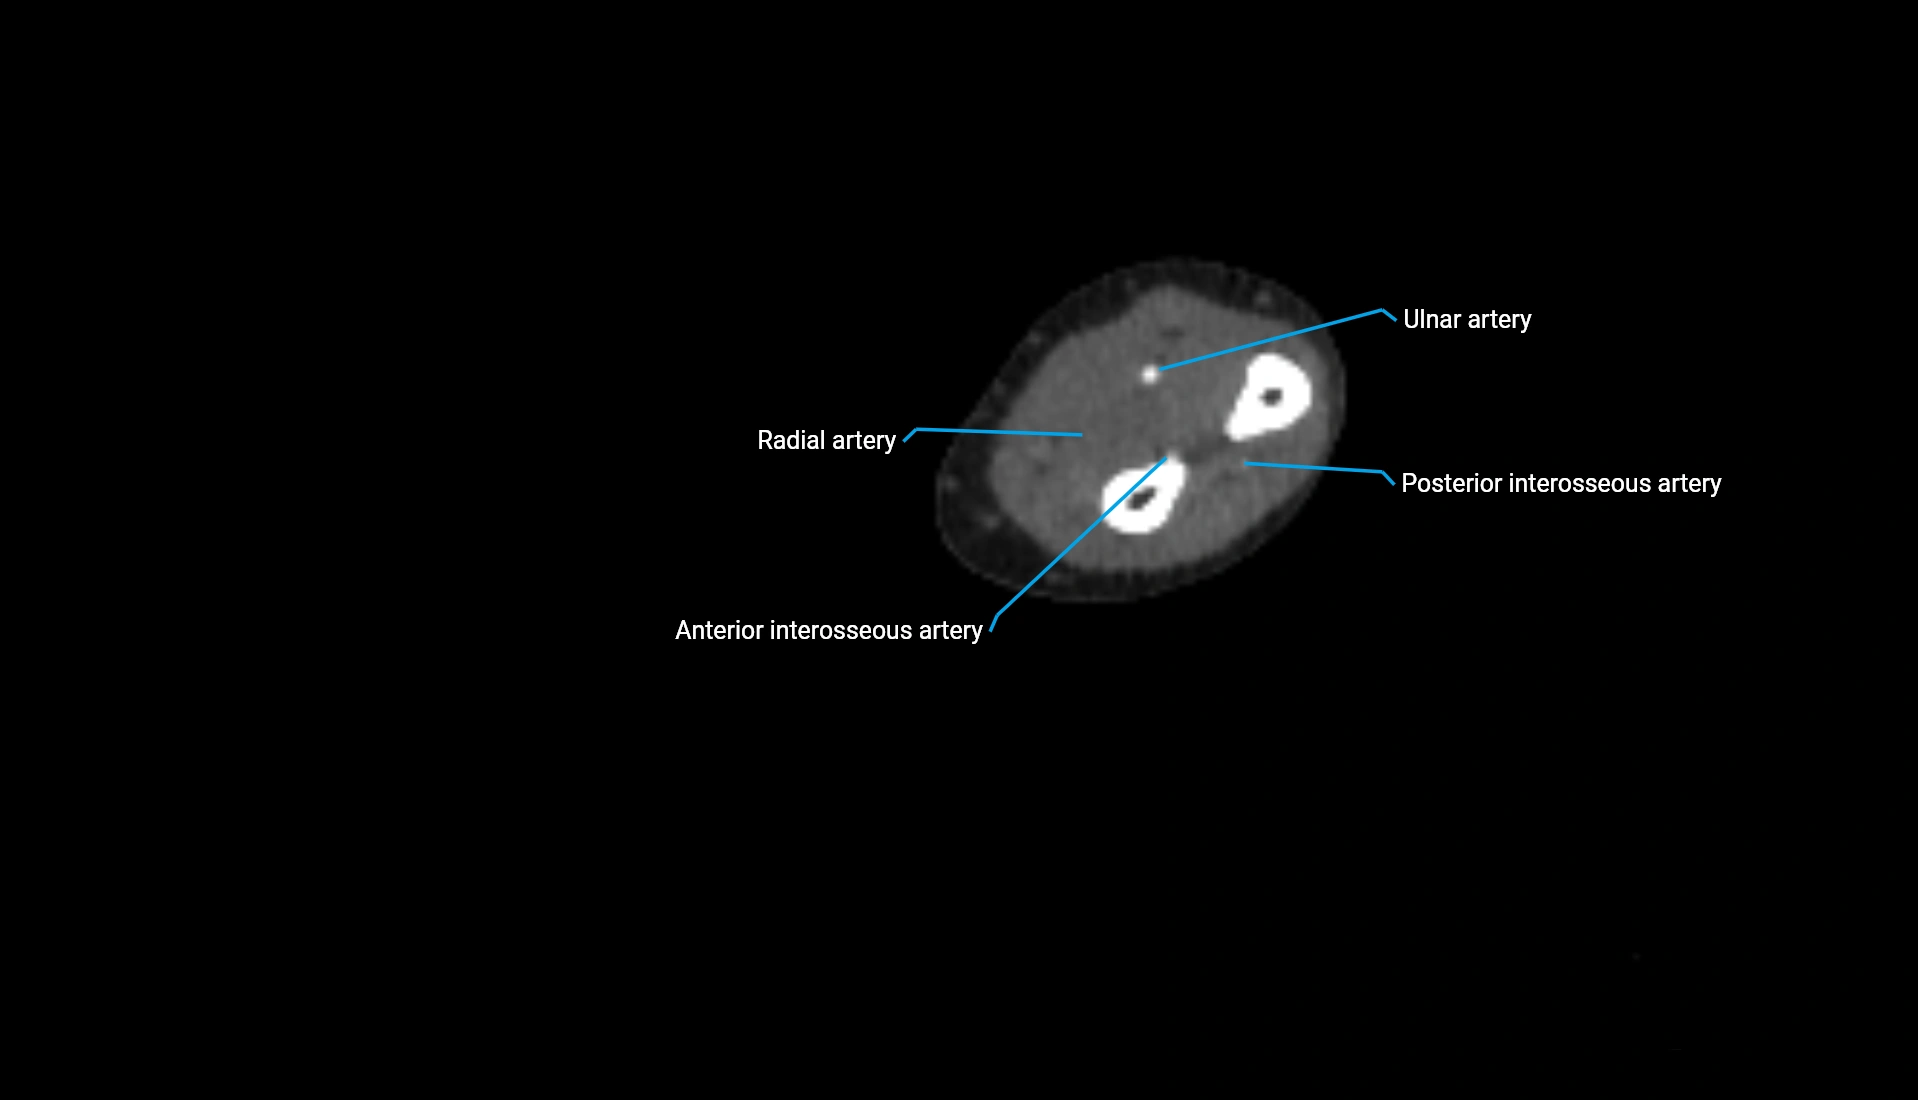

CT Appearance

Non-Contrast CT:

• Cortex: High-density, sharply defined

• Subchondral bone: Dense cancellous matrix

• Articular surface: Smooth concave contour articulating with the capitellum

• Excellent for evaluating bone integrity, alignment, and subtle fractures